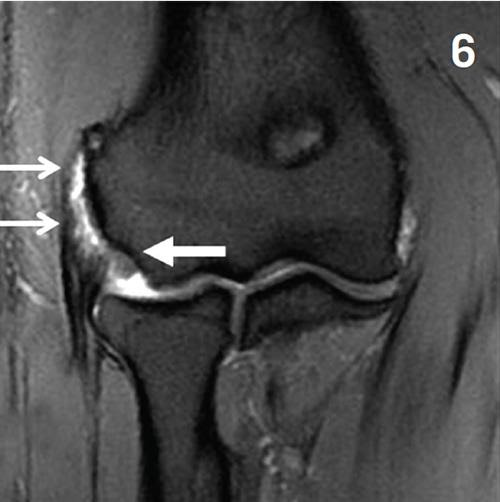

This MRI image shows a 45-year-old tennis player with chronic lateral elbow pain and a clinical diagnosis of tennis elbow. The intermediate-weighted (IW) fat suppressed fast spin echo sequences of the elbow shows thickening, and a bright area within the tendon that attaches to the lateral epicondyle of the humerus (small arrows). Note that the attachment of the thick triangular tendon at the proximal aspect of the ulna (large arrow) is intact but is thickened and irregular.